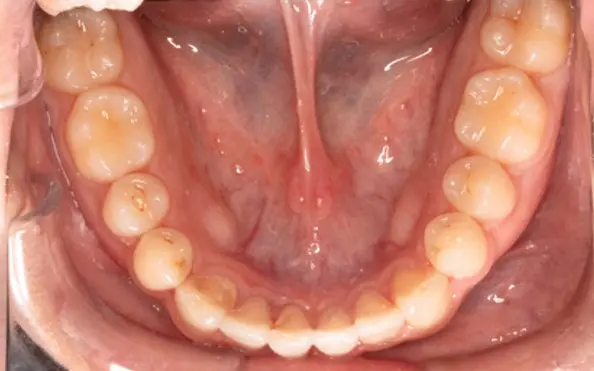

Before

After